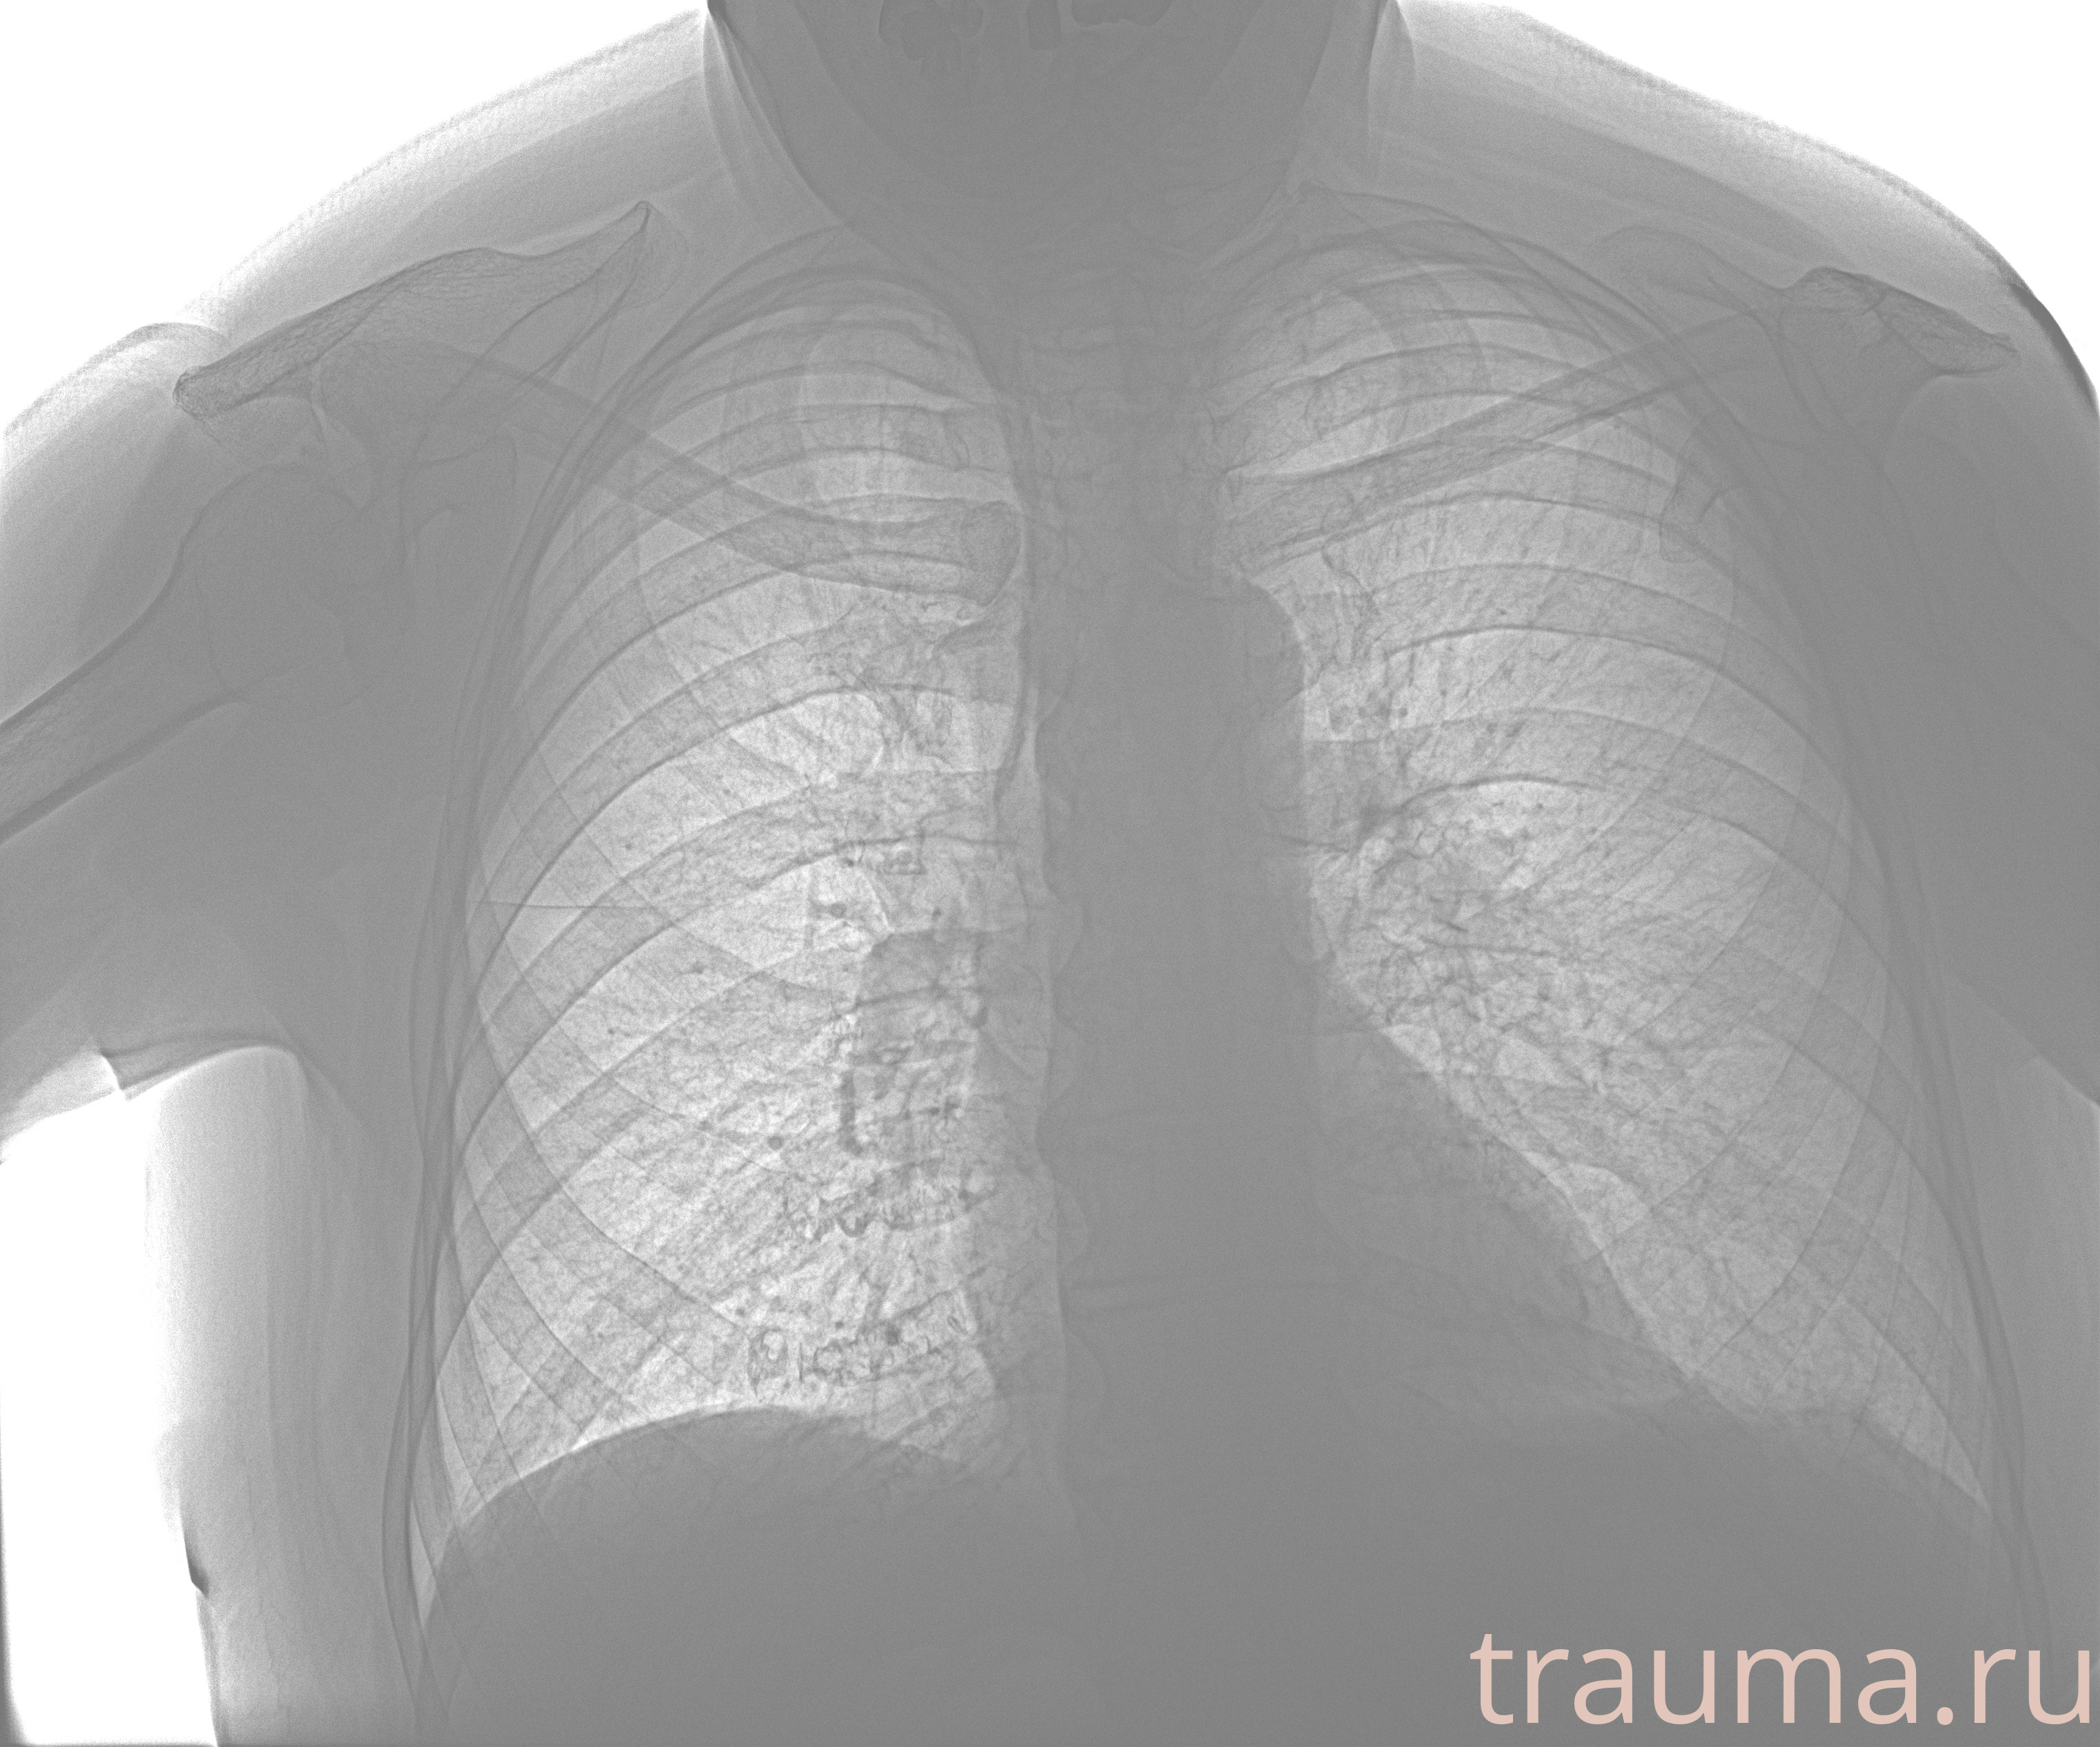

Рентген на дому: по вашему адресу приезжает врач-рентгенолог, травматолог-ортопед с мобильным рентгеновским аппаратом, проводит диагностику травмы или заболевания, делает необходимые рентгенограммы, дает рекомендации по дальнейшему лечению. Получить качественные снимки в домашних условиях возможно благодаря уникальной методике, разработанной МосРентген Центром для института  Склифосовского

при переломе шейки бедра и пневмонии от компании МосРентген Центр - партнера Института имени Склифосовского